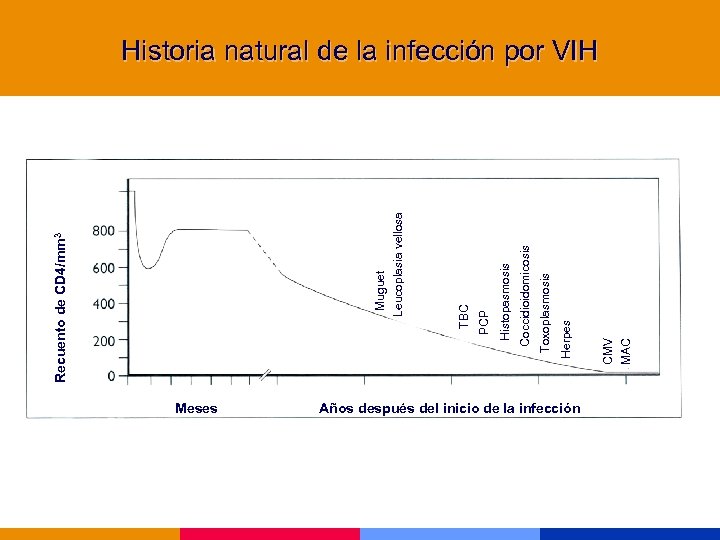

Historia natural de la infección por VIH

Historia natural de la infección por VIH

Meses Años después del inicio de la infección CMV MAC Herpes Toxoplasmosis Coccidioidomicosis Histopasmosis PCP TBC Muguet Leucoplasia vellosa Recuento de CD 4/mm 3 Historia natural de la infección por VIH

Meses Años después del inicio de la infección CMV MAC Herpes Toxoplasmosis Coccidioidomicosis Histopasmosis PCP TBC Muguet Leucoplasia vellosa Recuento de CD 4/mm 3 Historia natural de la infección por VIH